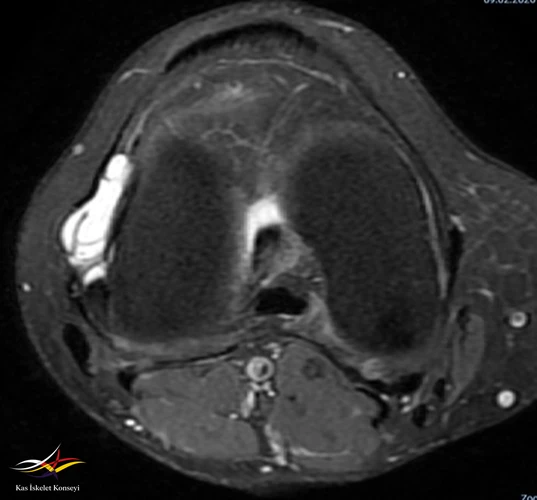

• Sağ diz MRG: Sağ diz ekleminde tibiofemoral ve patellofemoral eklem mesafeleri doğal olup, eklem yüzeyinde kartilaj yapı kalınlık ve sinyal intensiteleri tabiidir. Lateral menisküste longitudinal seyirli ve periferik uzanımlı rüptür ile lateral komşuluğunda LCL'yi deplase eden 22x32 mm boyutlu lobüle konturlu septalı parameniskal kist izlenmiştir. Medial menisküsün morfoloji ve sinyal intensite dağılımı doğal izlenmiş olup, patolojik sinyal intensite değişikliği saptanmamıştır. ACL, PCL'de hafif sprain mevcut olup, MCL, LCL tabiidir. Patellar ve quadriceps tendonların bütünlük ve sinyal intensiteleri tabiidir.